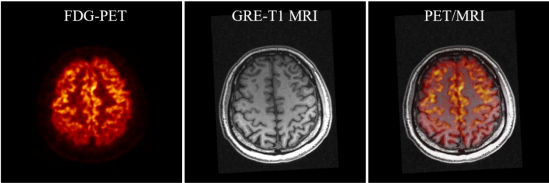

杨永峰介绍道,与国外商业磁兼容脑PET成像仪器相比,SIAT bPET的效率提高了近2倍(从7.2%到14%),平均体分辨率提高了30倍以上(从约64mm3到2mm3)。同时,SIAT bPET采用了创新的电子学和磁兼容设计,使得磁共振成像对PET成像的影响几乎可以忽略不计,PET成像对磁共振成像图像信噪比的影响小于5%,满足同时召开PET/MRI成像的尖端科研需求。

SIAT bPET和联影uMR790 3T磁共振成像系统上同时取得的人脑PET/MRI图像